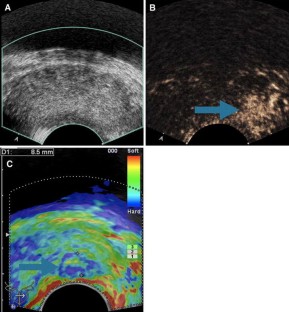

Fig. 1

A total of 133 men with elevated PSA serum levels (≥1.25 ng/mL) showed PCa suspicious lesions on E-TRUS. RTE was done to assess tissue elasticity, and hard areas of the peripheral zone were considered suspicious for malignancy. CE-TRUS was done with cadence contrast pulse sequencing (CPS) technique to assess tumor neoangiogenesis, which were defined as areas with increased and rapid contrast enhancement in the peripheral zone and were considered suspicious for malignancy. All patients underwent an E-TRUS-targeted biopsy of the prostate into the suspected lesions. PCa detection rates for E-TRUS were analyzed.